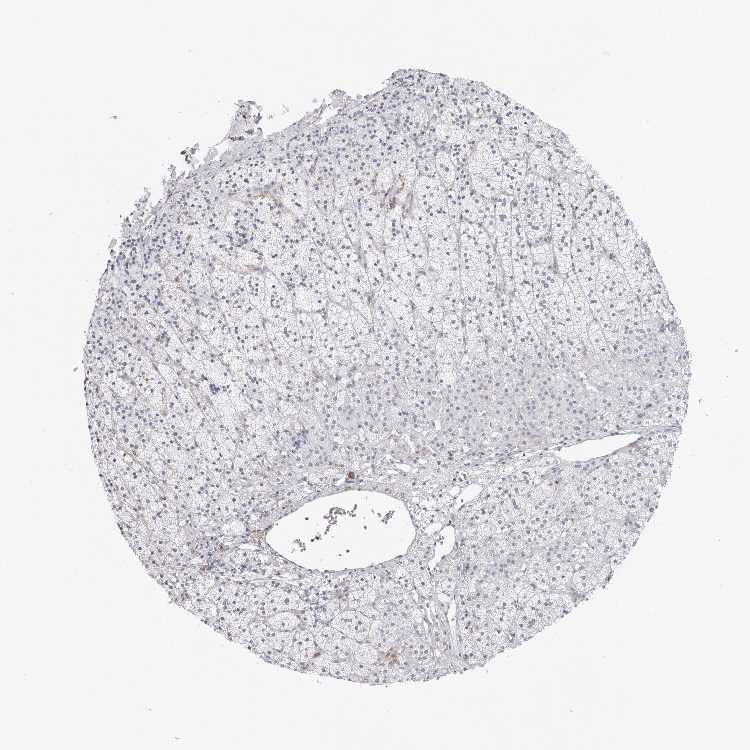

ADRENAL GLAND - Antibody stainingi

Antibody staining in the annotated cell types in the current human tissue is reported as not detected, low, medium, or high, based on conventional immunohistochemistry profiling in selected tissues. This score is based on the combination of the staining intensity and fraction of stained cells.

Each image is clickable and will lead to virtual microscopy that enables deeper exploration of all samples and also displays staining intensity scores, fraction scores and subcellular localization as well as patient and tissue information for each sample.

Antibody HPA008129Antibody HPA028288

Glandular cells Not detectedNot detected